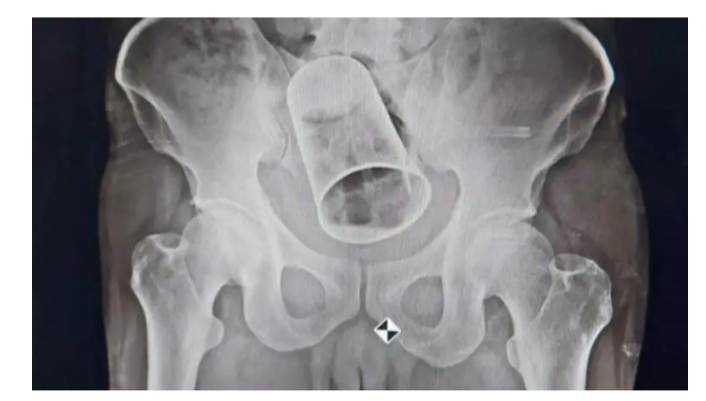

ಆಸ್ಪತ್ರೆ ಸೇರಿದ ಈತನ ಅವಸ್ಥೆ ಕಂಡು ನಿಜಕ್ಕೂ ಡಾಕ್ಟರ್ ದಿಗಿಲು ಗೊಂಡಿದ್ದರೆಂದೇ ಹೇಳಬಹುದು. ಸ್ಕ್ಯಾನಿಂಗ್ ಮೂಲಕ ಡಾಕ್ಟರ್ ಗೆ ಅಸಲಿ ಸತ್ಯ ತಿಳಿದಿದೆ. ನಂತರ ವೈದ್ಯರು ಮೊದಲು ಗುದನಾಳದ ಮೂಲಕ ಗ್ಲಾಸ್ ಅನ್ನು ಹೊರತೆಗೆಯಲು ಪ್ರಯತ್ನಿಸಿದ್ದಾರೆ. ಆದರೆ ತಮ್ಮ ಪ್ರಯತ್ನ ವಿಫಲವಾದಾಗ ಆಸ್ಪತ್ರೆಯ ಶಸ್ತ್ರ ಚಿಕಿತ್ಸಾ ವಿಭಾಗದ ಮುಖ್ಯಸ್ಥರೊಂದಿಗೆ ಚರ್ಚಿಸಿ, ಅವರ ಸಲಹೆ ಮೇರೆಗೆ ಕೂಡಲೇ ಆತನಿಗೆ ಶಸ್ತ್ರಚಿಕಿತ್ಸೆ ಮಾಡಲಾಯಿತು. ಭಾನುವಾರ ಬೆಹಾರ್‌ಂಪುರ ನಗರದ ಎಂಕೆಸಿಜಿ ವೈದ್ಯಕೀಯ ಕಾಲೇಜು ಮತ್ತು ಆಸ್ಪತ್ರೆಯಲ್ಲಿ ವೈದ್ಯರು ವ್ಯಕ್ತಿಯ ಕರುಳಿನಿಂದ ಸ್ಟೀಲ್ ಗ್ಲಾಸ್ ಅನ್ನು ಶಸ್ತ್ರಚಿಕಿತ್ಸೆ ಮೂಲಕ ಹೊರತೆಗೆದು ಹಾಕಿದ್ದಾರೆ.